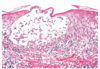

The histological sample below is due to what condition? What type of hypersensitivity reaction is it associated with?

Contact dermatitis caused by a type IV (T-cell mediated) hypersensitivity

Image annotation: Separation of epidermis from dermis. Filled with edematous fluid (spongiosus). Notice ring of inflammatory T-cells surrounding the fluid pocket.